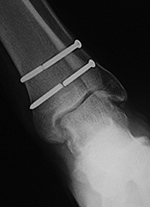

Left ankle syndesmotic screw fracturing |

22 year-old man with syndesmotic screw placement for medial avulsive ankle injury. The screws fractured and loosened and were later removed. |